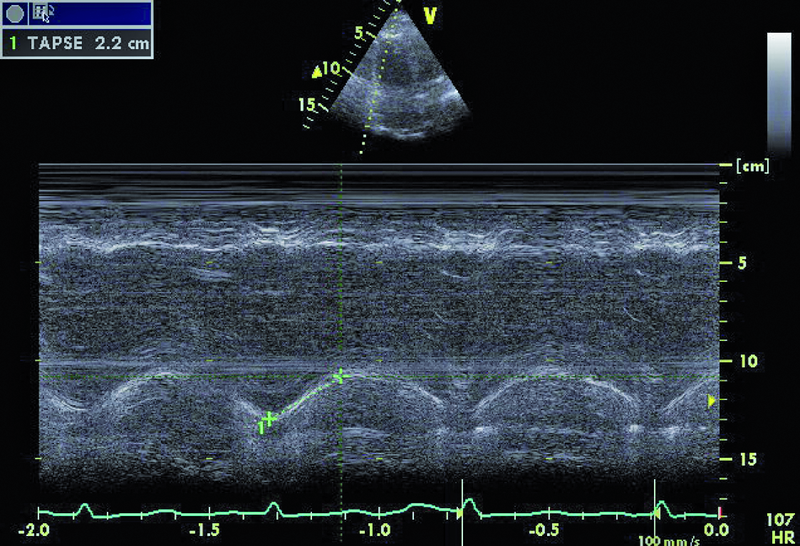

Dowodem klinicznym masywnej zatorowości płucnej był u chorej epizod omdlenia, utrzymująca się duszność, niskie ciśnienie tętnicze. Wiodącą rolę w rozpoznaniu choroby pełni tomografia komputerowa. Badanie echokardiograficzne uznawane jest za uzupełniające. Powiększenie jamy prawej komory stwierdzane w dniu hospitalizacji mówiło o możliwości istotnej dysfunkcji łożyska płucnego. Masywna zatorowość jest wskazaniem do włączenia leczenia fibrynolitycznego, zmniejszającego śmiertelność i zapobiegającego nawrotom choroby. Stan kliniczny pacjentki w wyniku zastosowanej alteplazy poprawił się. Rejestrowano zmniejszenie stężenia d-dimeru i troponiny. Czy jednak sytuacja chorej nie budzi już niepokoju? Mimo ograniczonej jakości przedstawionych rycin można dostrzec, że jama prawej komory jest przeciążona (ryc. 1, 2), a ciśnienie w łożysku tętnic płucnych szacowane z czasu akceleracji wypływu (66 ms!) jest podwyższone (ryc. 3). Im większa jest obstrukcja łożyska płucnego, tym więcej cech dysfunkcji prawej komory stwierdza się w badaniu ultradźwiękowym. Warunki obrazowania utrudniały odniesienie się do odcinkowej kurczliwości ściany wolnej i potwierdzenie lub wykluczenie objawu McConnella, czyli dysfunkcji segmentu środkowego. Ze względu na trudność w wizualizacji wsierdzia nie można było także ocenić zmiany pola powierzchni prawej komory (RV FAC). Mimo zachowanej funkcji kurczliwej prawej komory mierzonej wartością przemieszczenia pierścienia trójdzielnego (ryc. 4) uważny czytelnik z pewnością dostrzeże tkwiącą w prawej tętnicy płucnej skrzeplinę (ryc. 5, 6). Rzadko udaje się bezpośrednio uwidocznić skrzeplinę w łożysku tętnic płucnych. Kontrolne badanie TK klatki piersiowej potwierdziło obecność tzw. zatoru jeźdźca w pniu płucnym ze skrzeplinami w gałęzi prawej i gałęziach segmentalnych do płata dolnego prawego płuca. Obserwowano jedynie częściową regresję skrzeplin z tętnic płatowych i segmentalnych. Mamy więc do czynienia z nieskutecznością leczenia fibrynolitycznego (no clot resolution). Dobry stan kliniczny chorej nie wskazywał na potrzebę zastosowania leczenia chirurgicznego i embolektomii. Nie podjęto także decyzji o powtórnym leczeniu fibrynolitycznym z użyciem innego środka. Postanowiono kontynuować leczenie przeciwkrzepliwe i przeprowadzić po kilku tygodniach ponowną ocenę stanu klinicznego pacjentki i stanu łożyska tętnic płucnych. Wobec wieku chorej i licznych obciążeń internistycznych interesującą opcją leczenia (ale niestosowaną w tutejszym ośrodku) byłaby trombektomia za pomocą cewnika z miejscowym podaniem leczenia fibrynolitycznego.